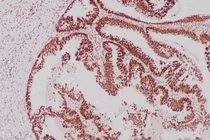

Nhưng kết quả nội soi thực quản - dạ dày - tá tràng bằng kỹ thuật nội soi phóng đại kết hợp nội soi NBI (dải tần ánh sáng hẹp) cho thấy nhiều bất thường: Viêm teo niêm mạc dạ dày C2; Dị sản ruột lan rộng (EGGIM 6 điểm), tức nguy cơ cao tiến triển ung thư dạ dày; Sẹo loét hành tá tràng; Nhiễm vi khuẩn HP.

BSNT Phạm Văn Quang, Chuyên khoa Tiêu hóa, Trung tâm Tiêu hóa Medlatec cho biết: “Trường hợp của anh M. gần như không có bất kỳ triệu chứng lâm sàng nào, ngoài biểu hiện thừa cân. Nếu không chủ động kiểm tra sức khỏe định kỳ và nội soi tiêu hóa chuyên sâu có thể bỏ sót các bất thường sức khỏe, đặc biệt là tổn thương dị sản ruột lan rộng - một yếu tố làm tăng nguy cơ ung thư dạ dày nhưng rất dễ bị bỏ sót”.